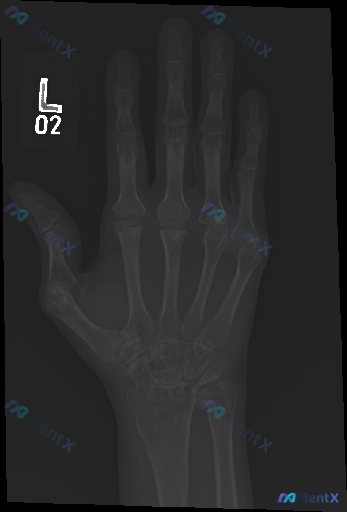

各位同道,这里有一份左手正位X光片的影像学表现供大家讨论。 影像观察 - 骨性结构:各掌骨及指骨皮质连续性尚可,未见明显新鲜骨折线及移位;腕骨排列大致有序,未见明显舟骨腰部骨折或钩骨骨折征象;整体骨密度未见明显异常,骨小梁结构清晰,未见明显局部溶骨性破坏或成骨性改变;受检者骨骺线均已闭合,提示为成年...